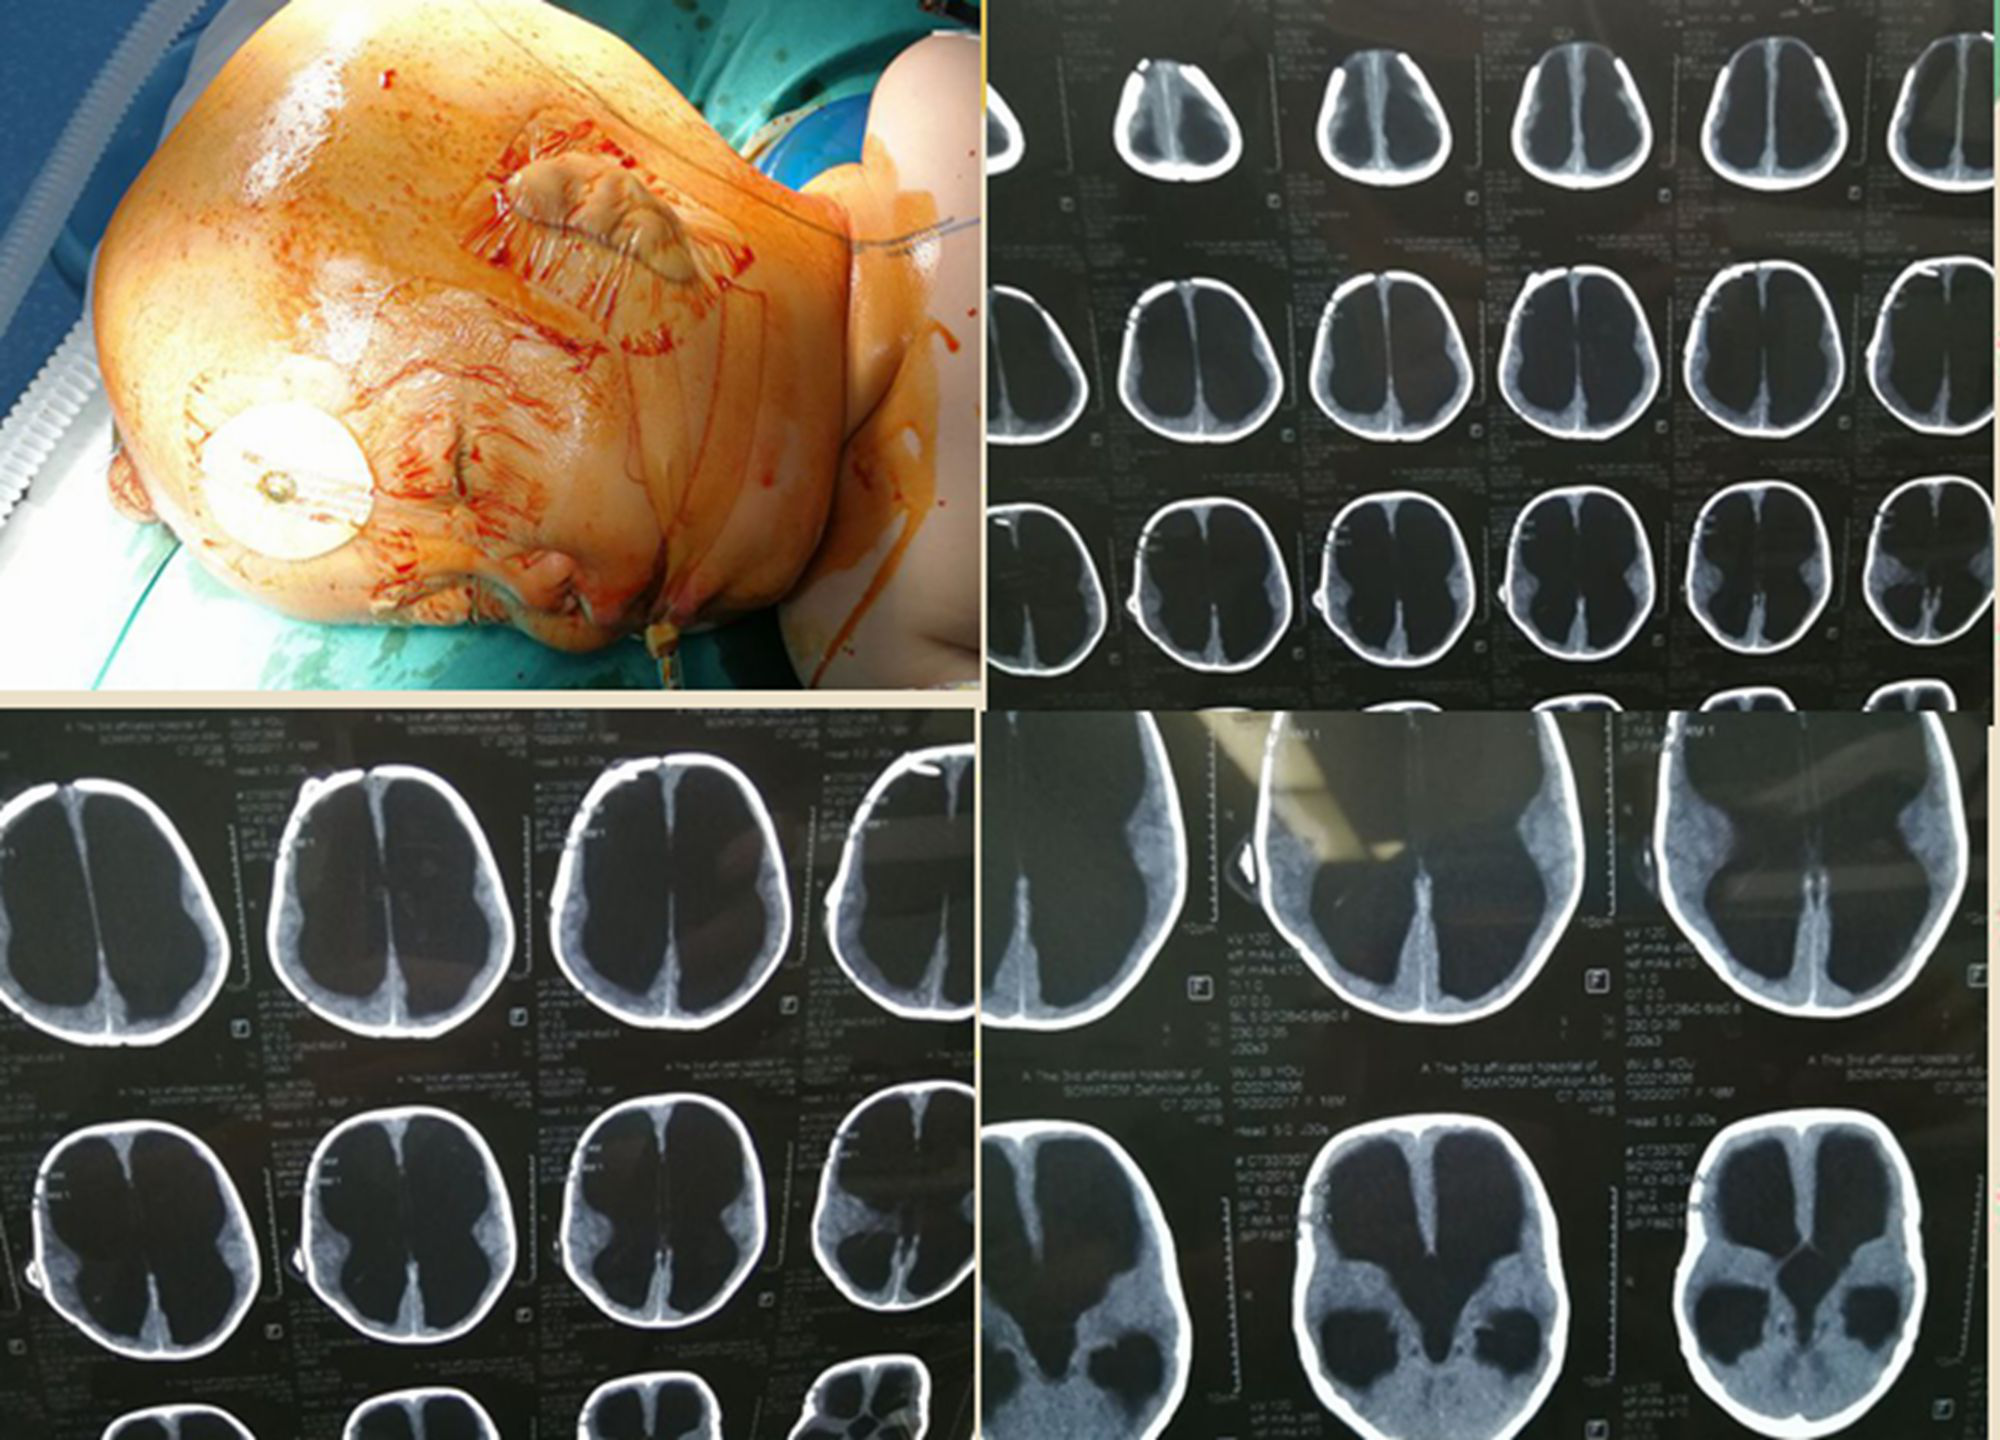

韦丽华儿子,周宇航脑积水手术

图片尺寸200x200